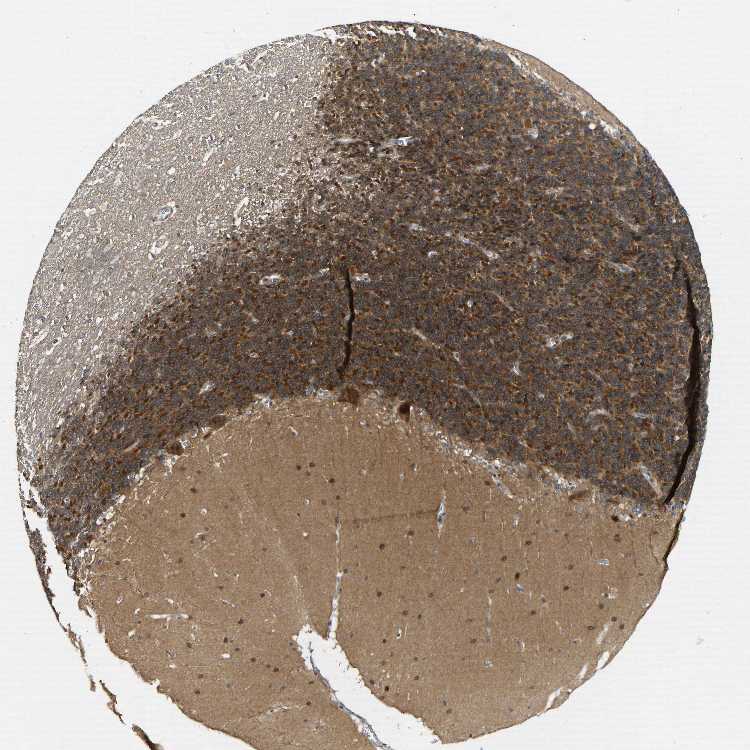

BRAIN CEREBELLUM Show tissue menu

CEREBELLUM - Expression summary

CEREBELLUM - Antibody stainingi

Antibody staining in the annotated cell types in the current human tissue is reported as not detected, low, medium, or high, based on conventional immunohistochemistry profiling in selected tissues. This score is based on the combination of the staining intensity and fraction of stained cells.

Each image is clickable and will lead to virtual microscopy that enables deeper exploration of all samples and also displays staining intensity scores, fraction scores and subcellular localization as well as patient and tissue information for each sample.

Antibody HPA017851

Purkinje cells High

Cells in granular layer High

Cells in molecular layer Medium